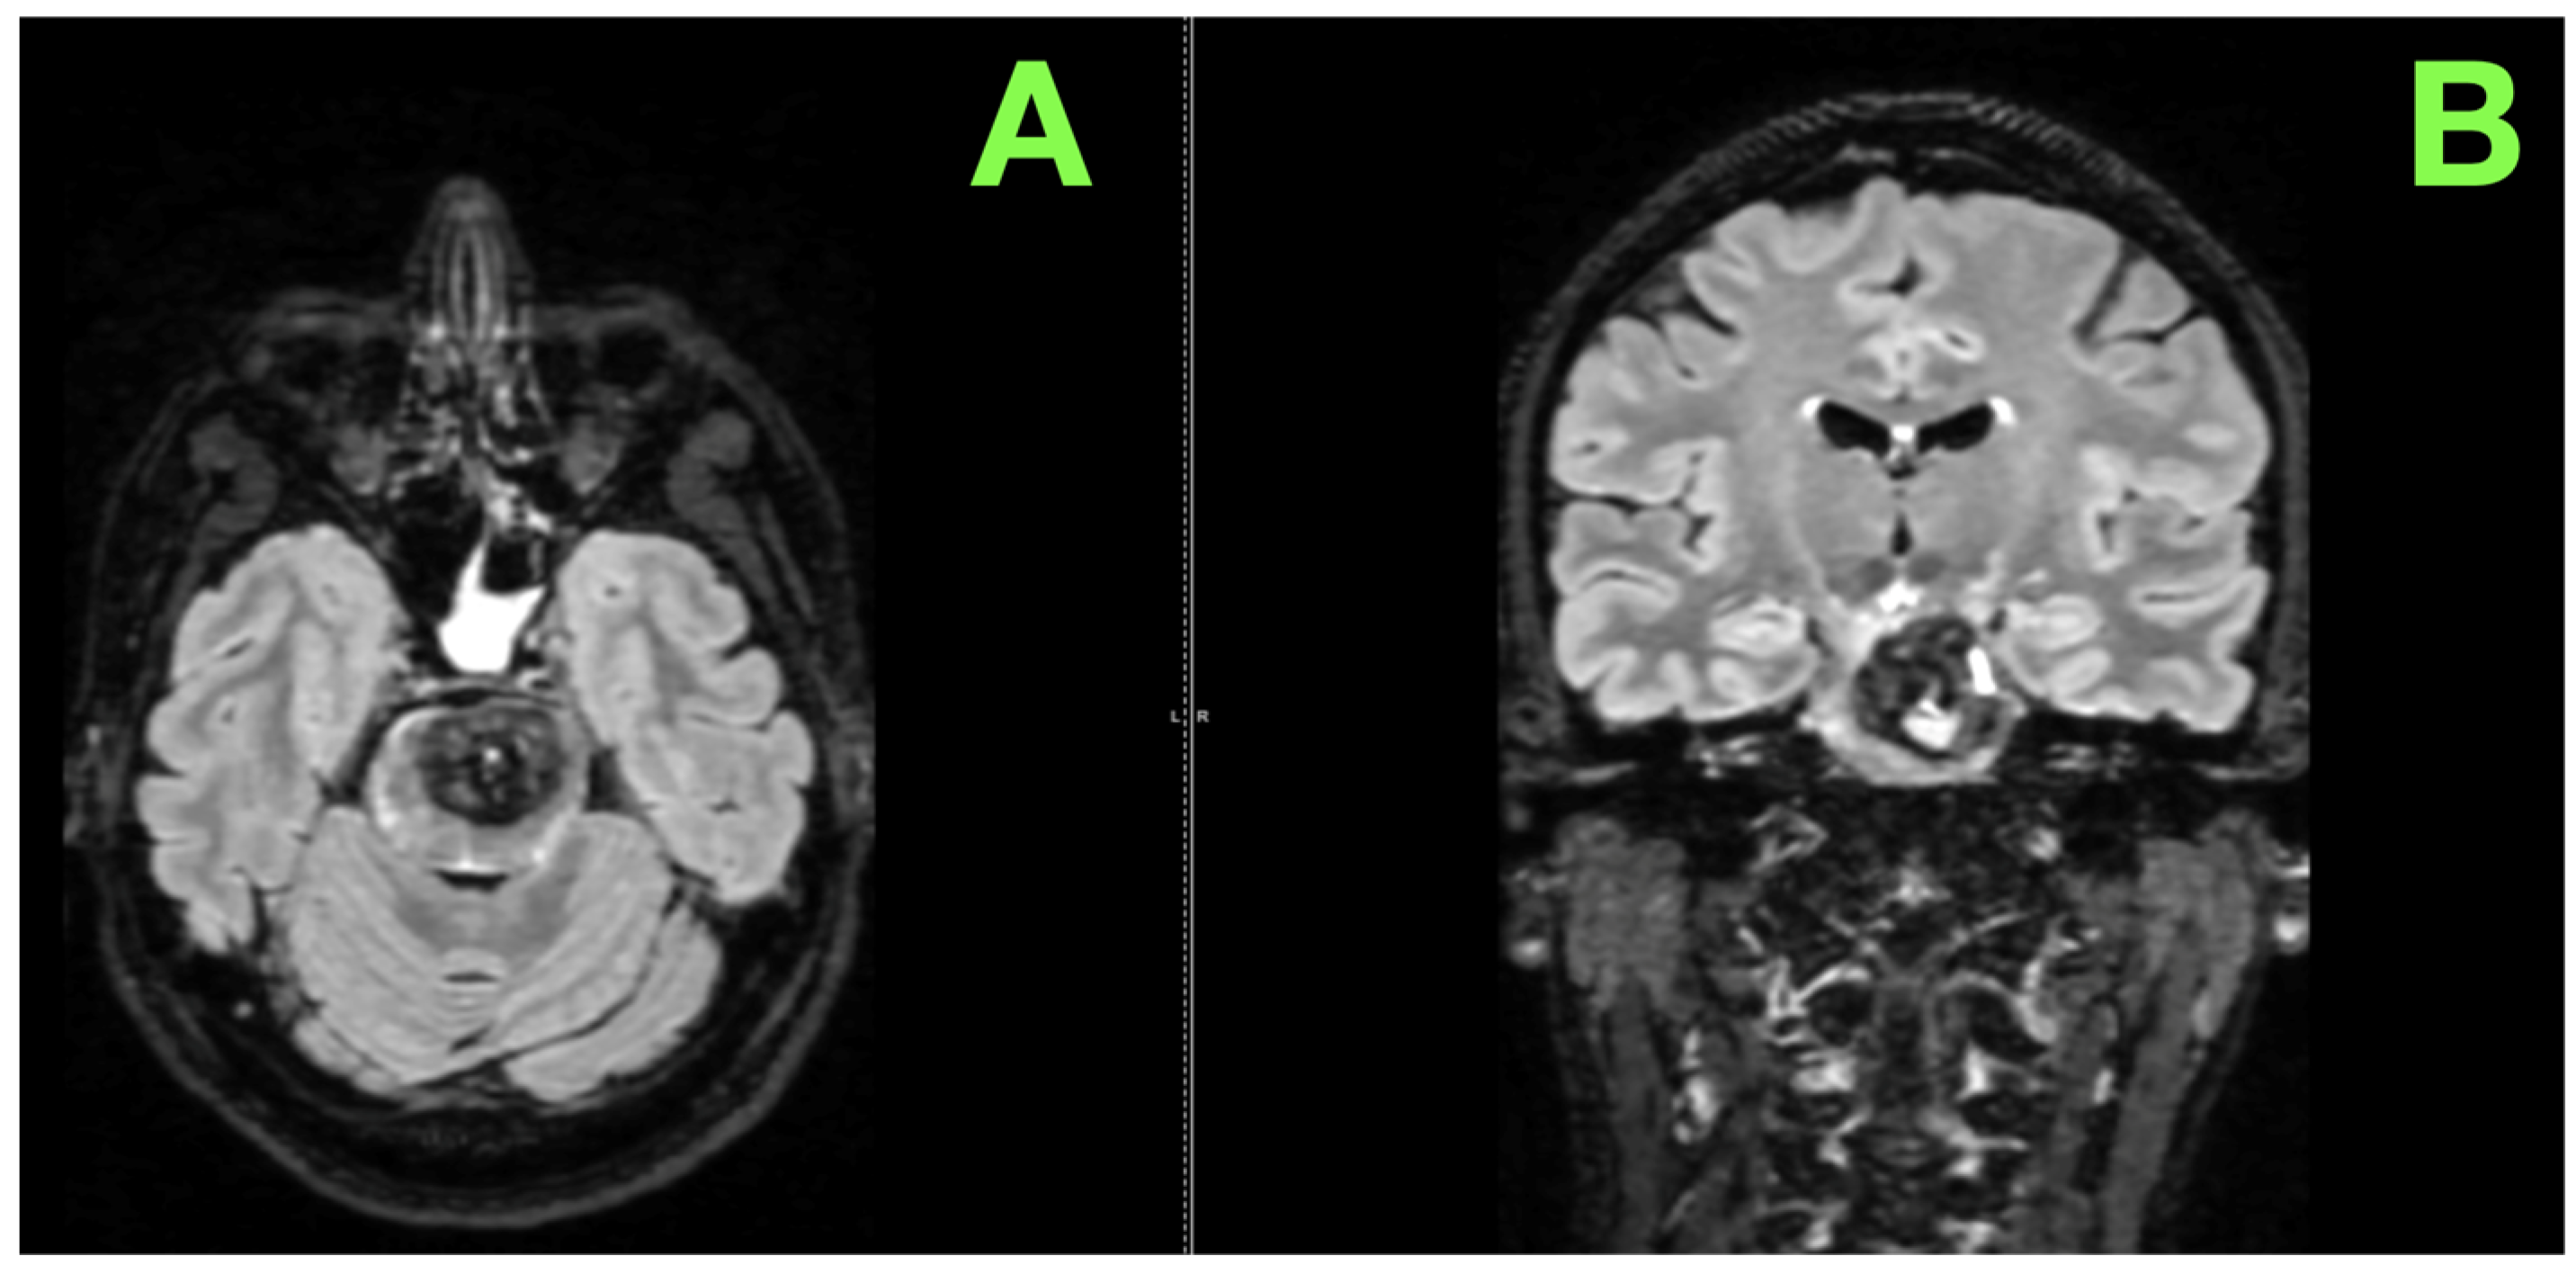

2. Case Presentation